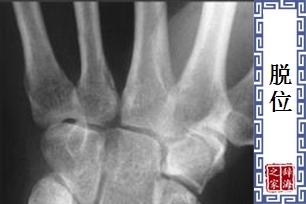

- 由于先天性的关节发育不全,病变或外伤等原因,造成关节的骨头发生移位,称为「脱位」。

【脱位】 图片鉴赏